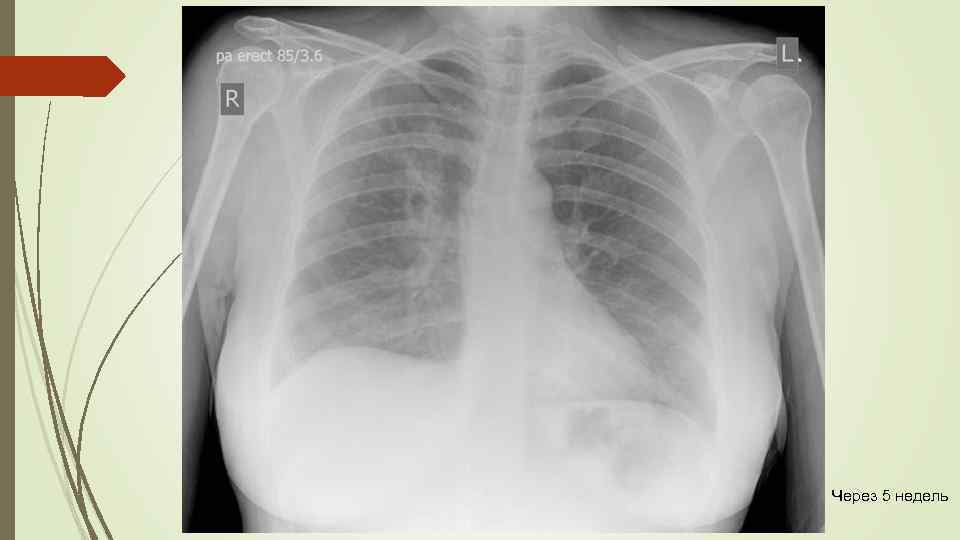

Через 5 недель

Через 5 недель